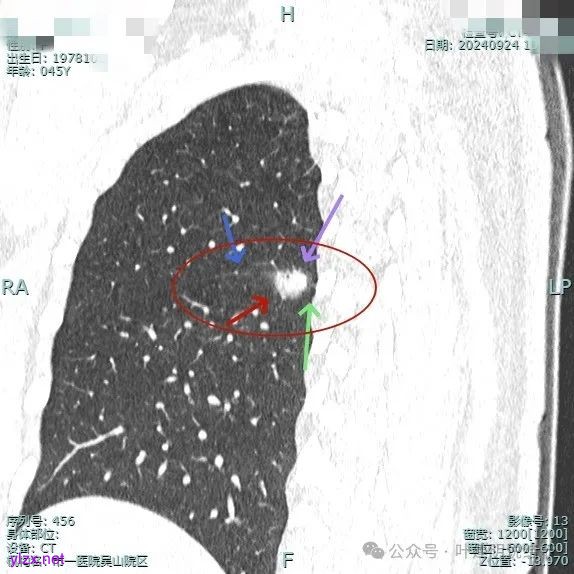

我们先来看2024年9月时的影像:

病灶2:

右中叶内侧段可见混合密度结节,大部分实性,形态与下叶背段的类似。

病灶1:

病灶是混合密度,边缘少许淡磨玻璃,灶内不太致密,表面不平,血管征有,但说不上明显异常增粗。

病灶紧贴叶间裂,而且感觉跨过肺叶,部分影响到上叶了,病灶本身密度虽实性为主,但是不太致密,有点松散的感觉。

总体实性部分密度较高,而磨玻璃部分密度较低,且瘤肺边界欠清,关键是跨叶间裂生长,这与肿瘤似乎不容易解释些。

毛刺有但不太锐利,磨玻璃有但偏淡,实性为但不太致密,叶间裂与之关系密切,病灶跨叶生长。

上图显得与肿瘤较为符合,但跨叶生长的话,侵袭力应该较强,可她这病灶较刚发现时进展并不太明显。

上图层面也较符合恶性,血管进入明显,有浅分叶的样子,整体觉得有一定收缩力与膨胀感。

病灶表面不平,混合密度,磨玻璃成分较淡。